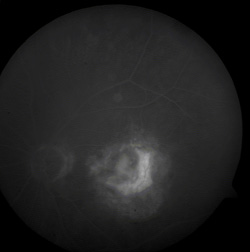

Rycina 2. Klasyczna postać CNV w AMD - fazy wczesne

Rola PDT polega na niszczeniu patologicznych naczyń podsiatkówkowych (CNV) przy użyciu podanego dożylnie związku fotouczulającego i promieniowania laserowego o niskiej mocy, które aktywuje związek skumulowany w patologicznych naczyniach. Przez wiele lat w takich przypadkach stosowano fotokoagulację laserową, ale tylko około 13- 26% pacjentów z CNV reagowało na leczenie, z czego około 50% leczonych miało nawrót przecieku. Z teoretycznego punktu widzenia jest duża przewaga PDT nad laserem konwencjonalnym. Ten ostatni działa termicznie, powodując obliterację nowotwórstwa podsiatkówkowego i zniszczenie leżącej powyżej sensorycznej siatkówki, podczas gdy metoda fotodynamiczna jest bardziej selektywna - dokładnie lokalizuje barwnik w obrębie CNV. Ponadto dawki promieniowania potrzebnego w leczeniu są dużo niższe niż wymagane do fotokoagulacji laserowej.

Do leczenia wykorzystuje się Visudyne, która jest preparatem handlowym vertoporfiryny. Vertoporfiryna jest lipofilnym fotosensybilizatorem II generacji z pikiem absorpcji między 680-695nm. Richter z zespołem odnotowali, że w porównaniu z Photofrinem (pierwszym fotouczulaczem zarejestrowanym przez FDA), vertoporfiryna jest około 4 razy bardziej skuteczna w pochłanianiu światła o długościach fali o najlepszej penetracji tkankowej (około 700nm) i jej zastosowanie doprowadza do około 10-krotnie silniejszego efektu cytotoksycznego w porównaniu z hematoporfiryną.

Leczenie polega na podaniu 6 mg/m2 powierzchni ciała Visudyny w ciągu 10 minut w postaci infuzji dożylnej, a następnie świeceniu poddołkowej zmiany, po 15 minutach od początku wlewu, wiązką promieniowania laserowego o długoścj fali 689nm. Zarówno gęstość energii, gęstość mocy wiązki laserowej, jak i czas zabiegu są stałe i wynoszą odpowiednio 50J/cm2, 600mW/cm2 i 83 sekundy. Wielkość wiązki lasera pokrywa się z największym wymiarem liniowym zmiany, do którego dodaje się margines 1000µm.